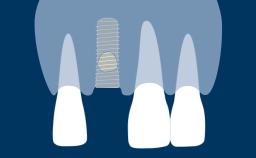

种植治疗是否成功受多个因素影响。这些因素包括种植治疗手术方面的基本要求。本模块将重点介绍一般口腔手术和外科种植手术的翻瓣设计基本原则。目的是确保在具有足够可见性和术区通路的情况下,尽可能无创伤地执行手术。

- 描述翻瓣设计的原则

- 描述种植手术的翻瓣设计原则

- 指出针对种植手术中特定情况的翻瓣设计